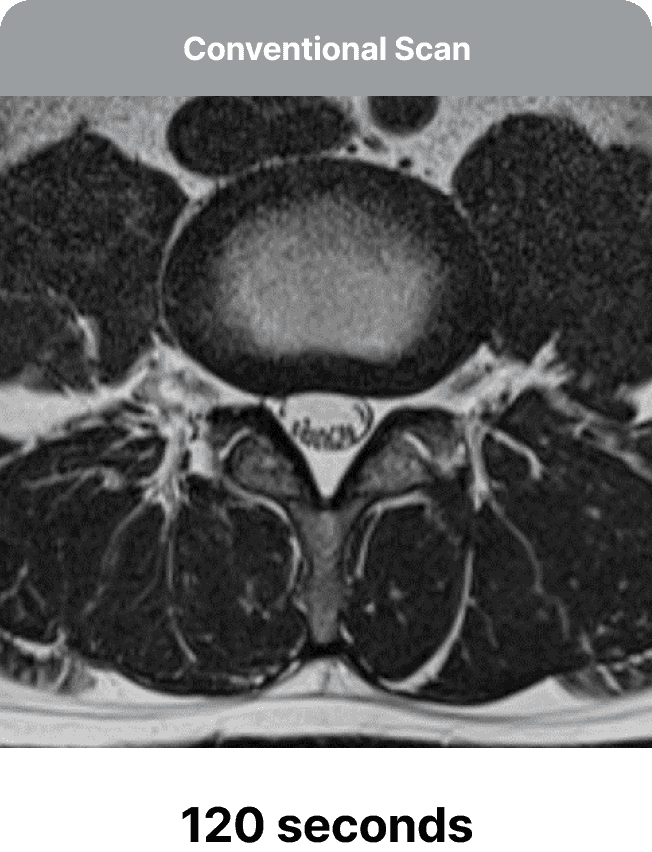

Το SwiftMR είναι μια λύση βαθιάς μάθησης που επιτρέπει τη μείωση του χρόνου σάρωσης MRI, ενισχύοντας την άνεση του ασθενούς χωρίς να θυσιάζει την ποιότητα της εικόνας. Η λύση επιτρέπει στα κέντρα ακτινολογίας να επιτύχουν νέα επίπεδα παραγωγικότητας και αποτελεσματικότητας, καθώς οι μικρότεροι χρόνοι σάρωσης αυξάνουν τη ροή ασθενών — ξεκλειδώνοντας ευκαιρίες για έσοδα και ανάπτυξη.

Η ομάδα μας θα βελτιστοποιήσει τα πρωτόκολλα MRI για να επιταχύνει τις σαρώσεις, παράγοντας αρχικά ταχύτερες αλλά χαμηλής ποιότητας εικόνες. Το μοντέλο βαθιάς μάθησης του SwiftMR στη συνέχεια χρησιμοποιείται για να βελτιώσει τις επιταχυνόμενες σαρώσεις, μετατρέποντάς τις αποτελεσματικά σε εικόνες υψηλής ποιότητας.